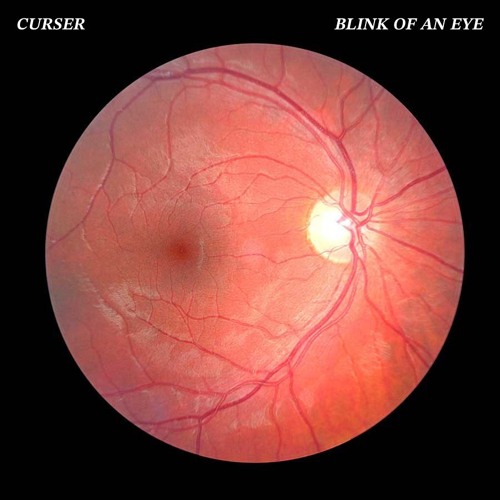

Изображения и анатомия сетчатки глаза